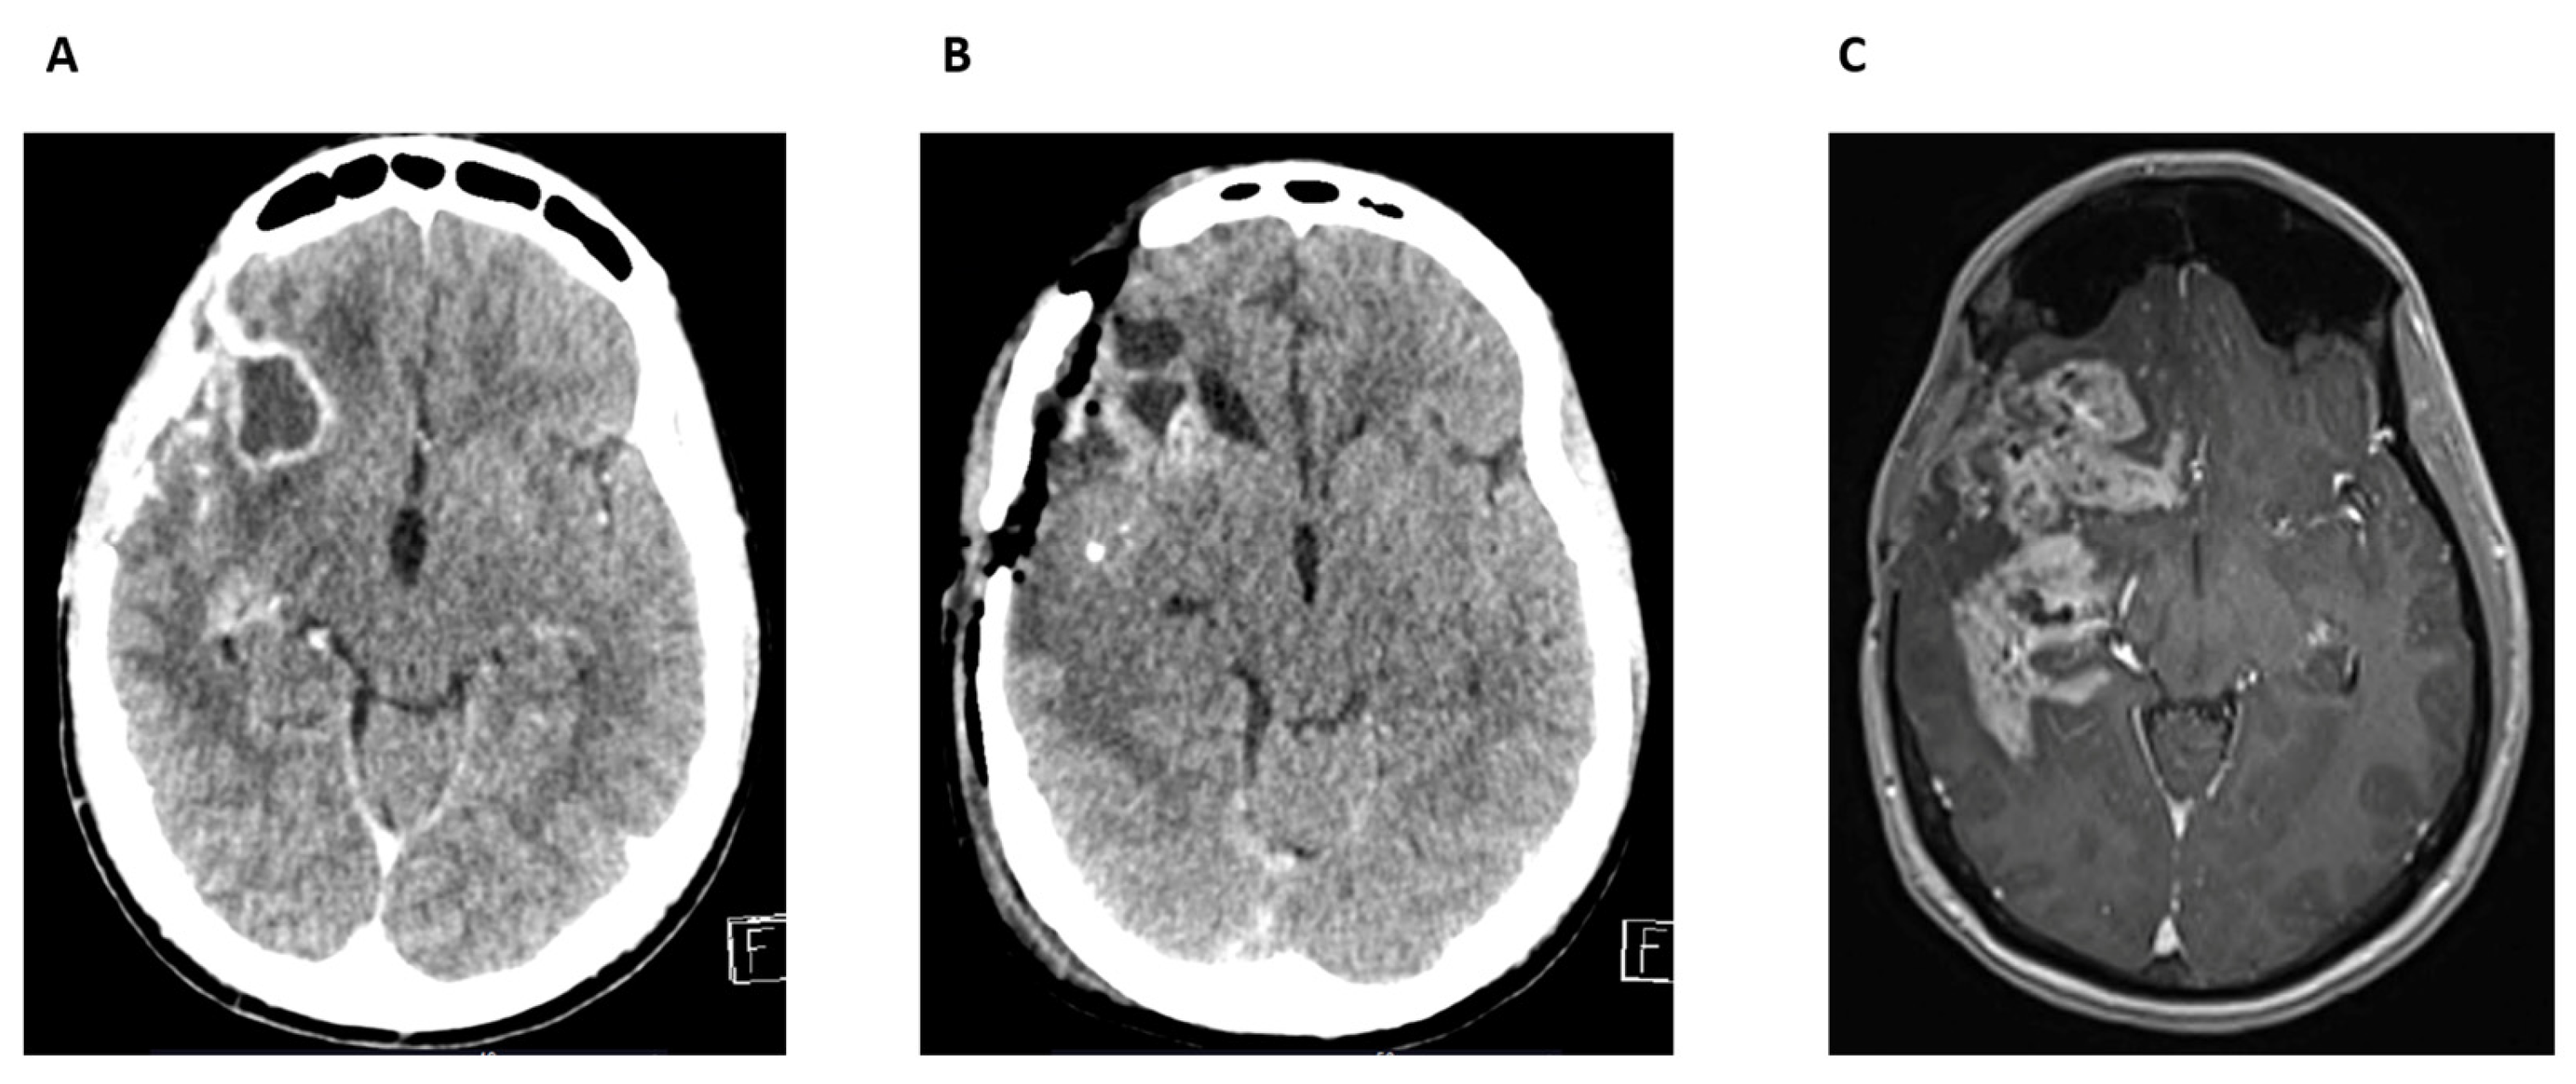

Case Report 1

Case Report 2

Case Report 3